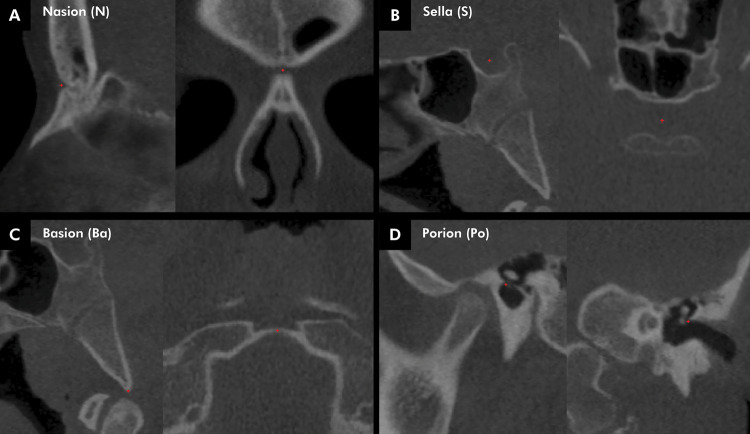

The aim of this cross-sectional study was to perform a three-dimensional (3D) assessment of the cranial base of patients with unilateral cleft lip and palate (UCLP). Cone-beam computed tomography (CBCT) scans of 52 UCLP patients (21 females and 31 males; mean age, 10.0 ± 2.12 years) were compared with the scans of 72 individuals (24 females and 48 males; mean age, 11.0 ± 2.11 years) without CLP, matched by gender and age (control group, CG). The 3D Euclidean distances of anterior cranial base (N-S), posterior cranial base (S-Ba), total cranial base (N-Ba) lengths, cranial base width (Po-Po), as well as the cranial base flexure (NSBa), were measured using open-source software ITK-SNAP and 3D Slicer. Statistical analyses were carried out with the Student's t-test at a significance level of 5%. UCLP demonstrated shorter 3D distances than CG in the N-S, S-Ba, and N-Ba cranial base lengths (p < 0.001). In comparison with female CG, female UCLP had a smaller cranial base flexure (NSBa; p = 0.020). No statistically significant differences between UCLP and CG were found for the cranial base width (Po-Po). UCLP patients presented distinct morphological cranial base characteristics in comparison with CG. These results indicate that morphological and positioning changes in the maxillary bones are not solely attributable to the cleft and/or surgical procedures.